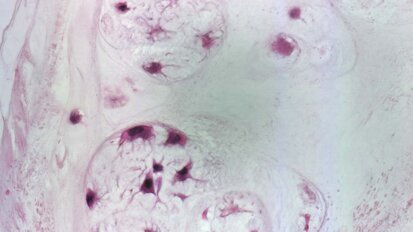

Nuove prospettive nella ricerca biomedica: cellule staminali di derivazione orale

Recentemente sono stati pubblicati i risultati delle Unità di Ricerca ammesse al cofinanziamento da parte del Ministero dell’Istruzione, ...

Riabilitazione delle lesioni al midollo spinale. Uno studio dei ricercatori del dentale

Hong Kong/Lipsia, Germania: negli ultimi anni, le cellule staminali dentarie sono state sempre più studiate per il loro utilizzo nelle applicazioni ...